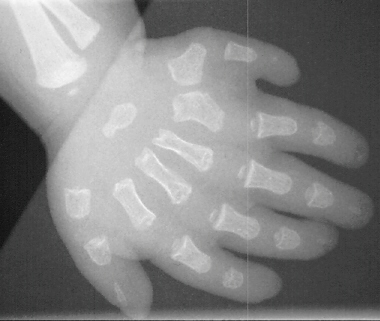

A 6 month old Amish infant female was referred for symmetric polydactyly of both hands. Prior to her presentation in our clinic she was seen and evaluated by a cardiologist for an apparent congenital heart murmur. On physical examination of the upper extremities there was a sixth digit on the ulnar border of both hands. The finger nails appeared to be dysplastic.

The heart murmur and extra digits are characteristics of the same syndrome.

As the child grows a short-limbed disproportionate dwarfism will likely become more apparent

This syndrome occurs most commonly in closed communities along the Eastern US, but has been reported in many ethnic groups.